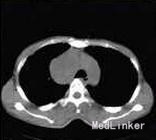

体检:体温37蘭80次,呼吸24次,血压120/80mmHg(1mmHg=0.133kPa)0精神疲惫,消瘦。全身浅表淋巴结未及肿大,心肺腹无明显异常。 皮肤科情况:双侧颊黏膜、上颚黏膜、舌边缘见多处溃瘍面;唇黏膜见片状糜烂面、渗出、黄色或黑褐色痂皮和嘴角浸溃发白,张口困难;鼻孔黏膜交界处、眼睑缘和阴茎冠状沟见浆痂和脱痂后的淡红斑;干、四肢见散在红斑和水疱,大疱疱壁紧贴皮肤、部分破裂,基底潮红,类似多形红斑样改变,部分疱液浑浊,见白色药痂黏着或黑色痂皮,尼氏征阴性;10指(趾)甲周见皱缩的水肿性暗红斑。 X线胸片:右上纵隔肿块5cmx6cmx7cm。 胸部CT:右前上纵隔内见一团状软组织肿块影,边界清楚,大小7.2cmx5.9cmx9.6cm,考虑:右前纵隔内肿块,巨淋巴结增生可能,心包少许积液;双肺散在少许炎症,双肺上叶多发性肺大泡。 背部水疱组织病理检査:轻度角化过度,部分基底细胞层上水疱,部分为棘层内水疱,水疱内见棘刺松解细胞,真皮浅层及血管周围散在淋巴细胞和嗜酸性粒细胞浸润;直接免疫荧光:棘细胞间IgG(±)、C3(++),基底膜带IgG(+),IgA和IgM均为阴性。符合天疱疮组织病理改变。